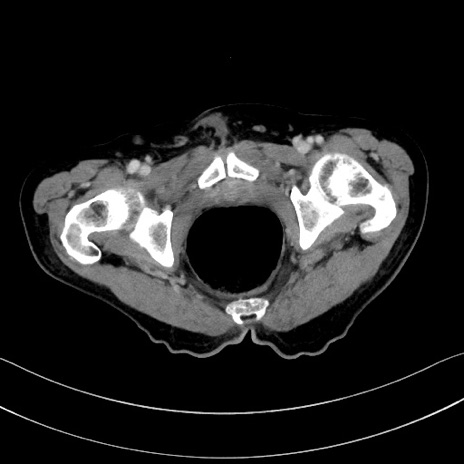

症例28(横断像)

【症例】60歳代男性

【主訴】嘔吐

【現病歴】胃癌にて胃全摘後。食思不振が悪化し、夜中に嘔吐することがある。

【既往歴】胃癌、胃全摘、脾摘、胆摘後

【データ】WBC 5900、CRP 10.56